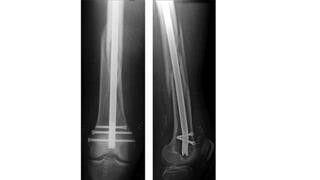

3) Retrograde IM nail :

Indications

• Good for supracondylar FRACTURE without significant comminution

• Preferred implant in osteoporotic bone

• Traditionally, 4 cm of intact distal femur needed but newer implants

with very distal interlocking options may decrease this number, can

perform independent screw stabilization of intercondylar component

of fracture around nail